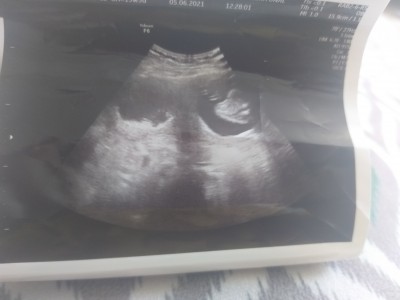

Arkadaşlar merhaba ben 19 hafta 6 günlük hamileyim dün hastaneye gittim Doktor sağ ve solda bir şey söyledi anlamadım gösterdi zararı var mı dedim ilaçlarını kullandığım sürece bebeğe bir zararı olmaz dedi ultrasyonda fotoğraf var anlayan olur mu acaba

Gebelik haftası 19.6

İkiz değil mi bu ne anlamadım kız

Yok canım ya ikiz değil işte 19 haftalık oldum Doktor sağda ve solda bir şey var dedi zararı olur mu dedim ilaçlarını kullandığınız sürece bir zararı olmaz dedi Ben de tam anlamadım mesaj attığımda tekrardan korktum acaba bebeğe bir zararı olur mu diye sizlere sormak istedim ben de Ne olduğunu anlamadım

Kanama alanimi sormadinizmi birsey ne diye..demistir ne oldugunu subkoryonik hematommu acaba

Sanırım kistin var canım ilaclarini düzgün kullan

kist olabilir mi canim bayada büyükmüs dr ilac verdiyse mutlaka kullan yumurtaliklarinda mi varmis

Bendede bebek kesesinin içinde amniyotik bant var sağda aceba sanada öyle bir şey demiş olabilirmi canım